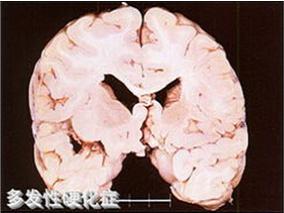

雌孕激素联合INF-β是否能改善MS女性的认知功能?

1小时条评论认知障碍是多发性硬化(MS)的一种致残的症状。虽然其管理仍具有挑战性,但是已有研究报道了干扰素-beta;(INF-beta;)在认知功能方面的获益,同时也提出了雌孕激素获益的假设,提示两种药物的组合在MS女性中会是一种有前景的治疗策略。2016年12月,《CNS Drugs》的...